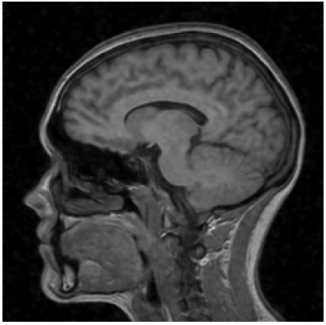

Super-resolution! This is an AI made image – they feed in the grainy one from above and try to produce the high quality one.

Here is the side by side comparison of the AI generated “denoised” image (on the left) and the diagnostic quality image (on the right).

If you look closely you can see that it isn’t perfect (there is still some blurring present), but the overall anatomy looks pretty reasonable. Nothing is horribly out of place, and maybe the blurring/quality issue is solvable with improved AI algorithms.